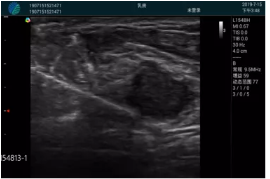

M20實(shí)時(shí)引導(dǎo):向包塊后方間隙注射利多卡因

清晰顯示腺體內(nèi)低回聲快影,邊界清晰,包膜較光滑

確定進(jìn)針路徑并實(shí)時(shí)監(jiān)測(cè)抽吸針與腫塊位置關(guān)系

抽吸針進(jìn)入腫塊內(nèi)部進(jìn)行旋切

抽吸過程中可見腫塊明顯縮小,并根據(jù)腫塊位置改變針道位置